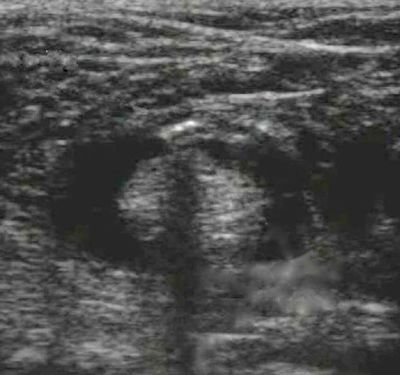

What is the phenomenon that MOST likely causes the sciatic nerve to appear severed in this image?

Answer

• Acoustic shadowing

• Acoustic enhancement

• Bayonet artifact

• Incorrect time gain compensation settings